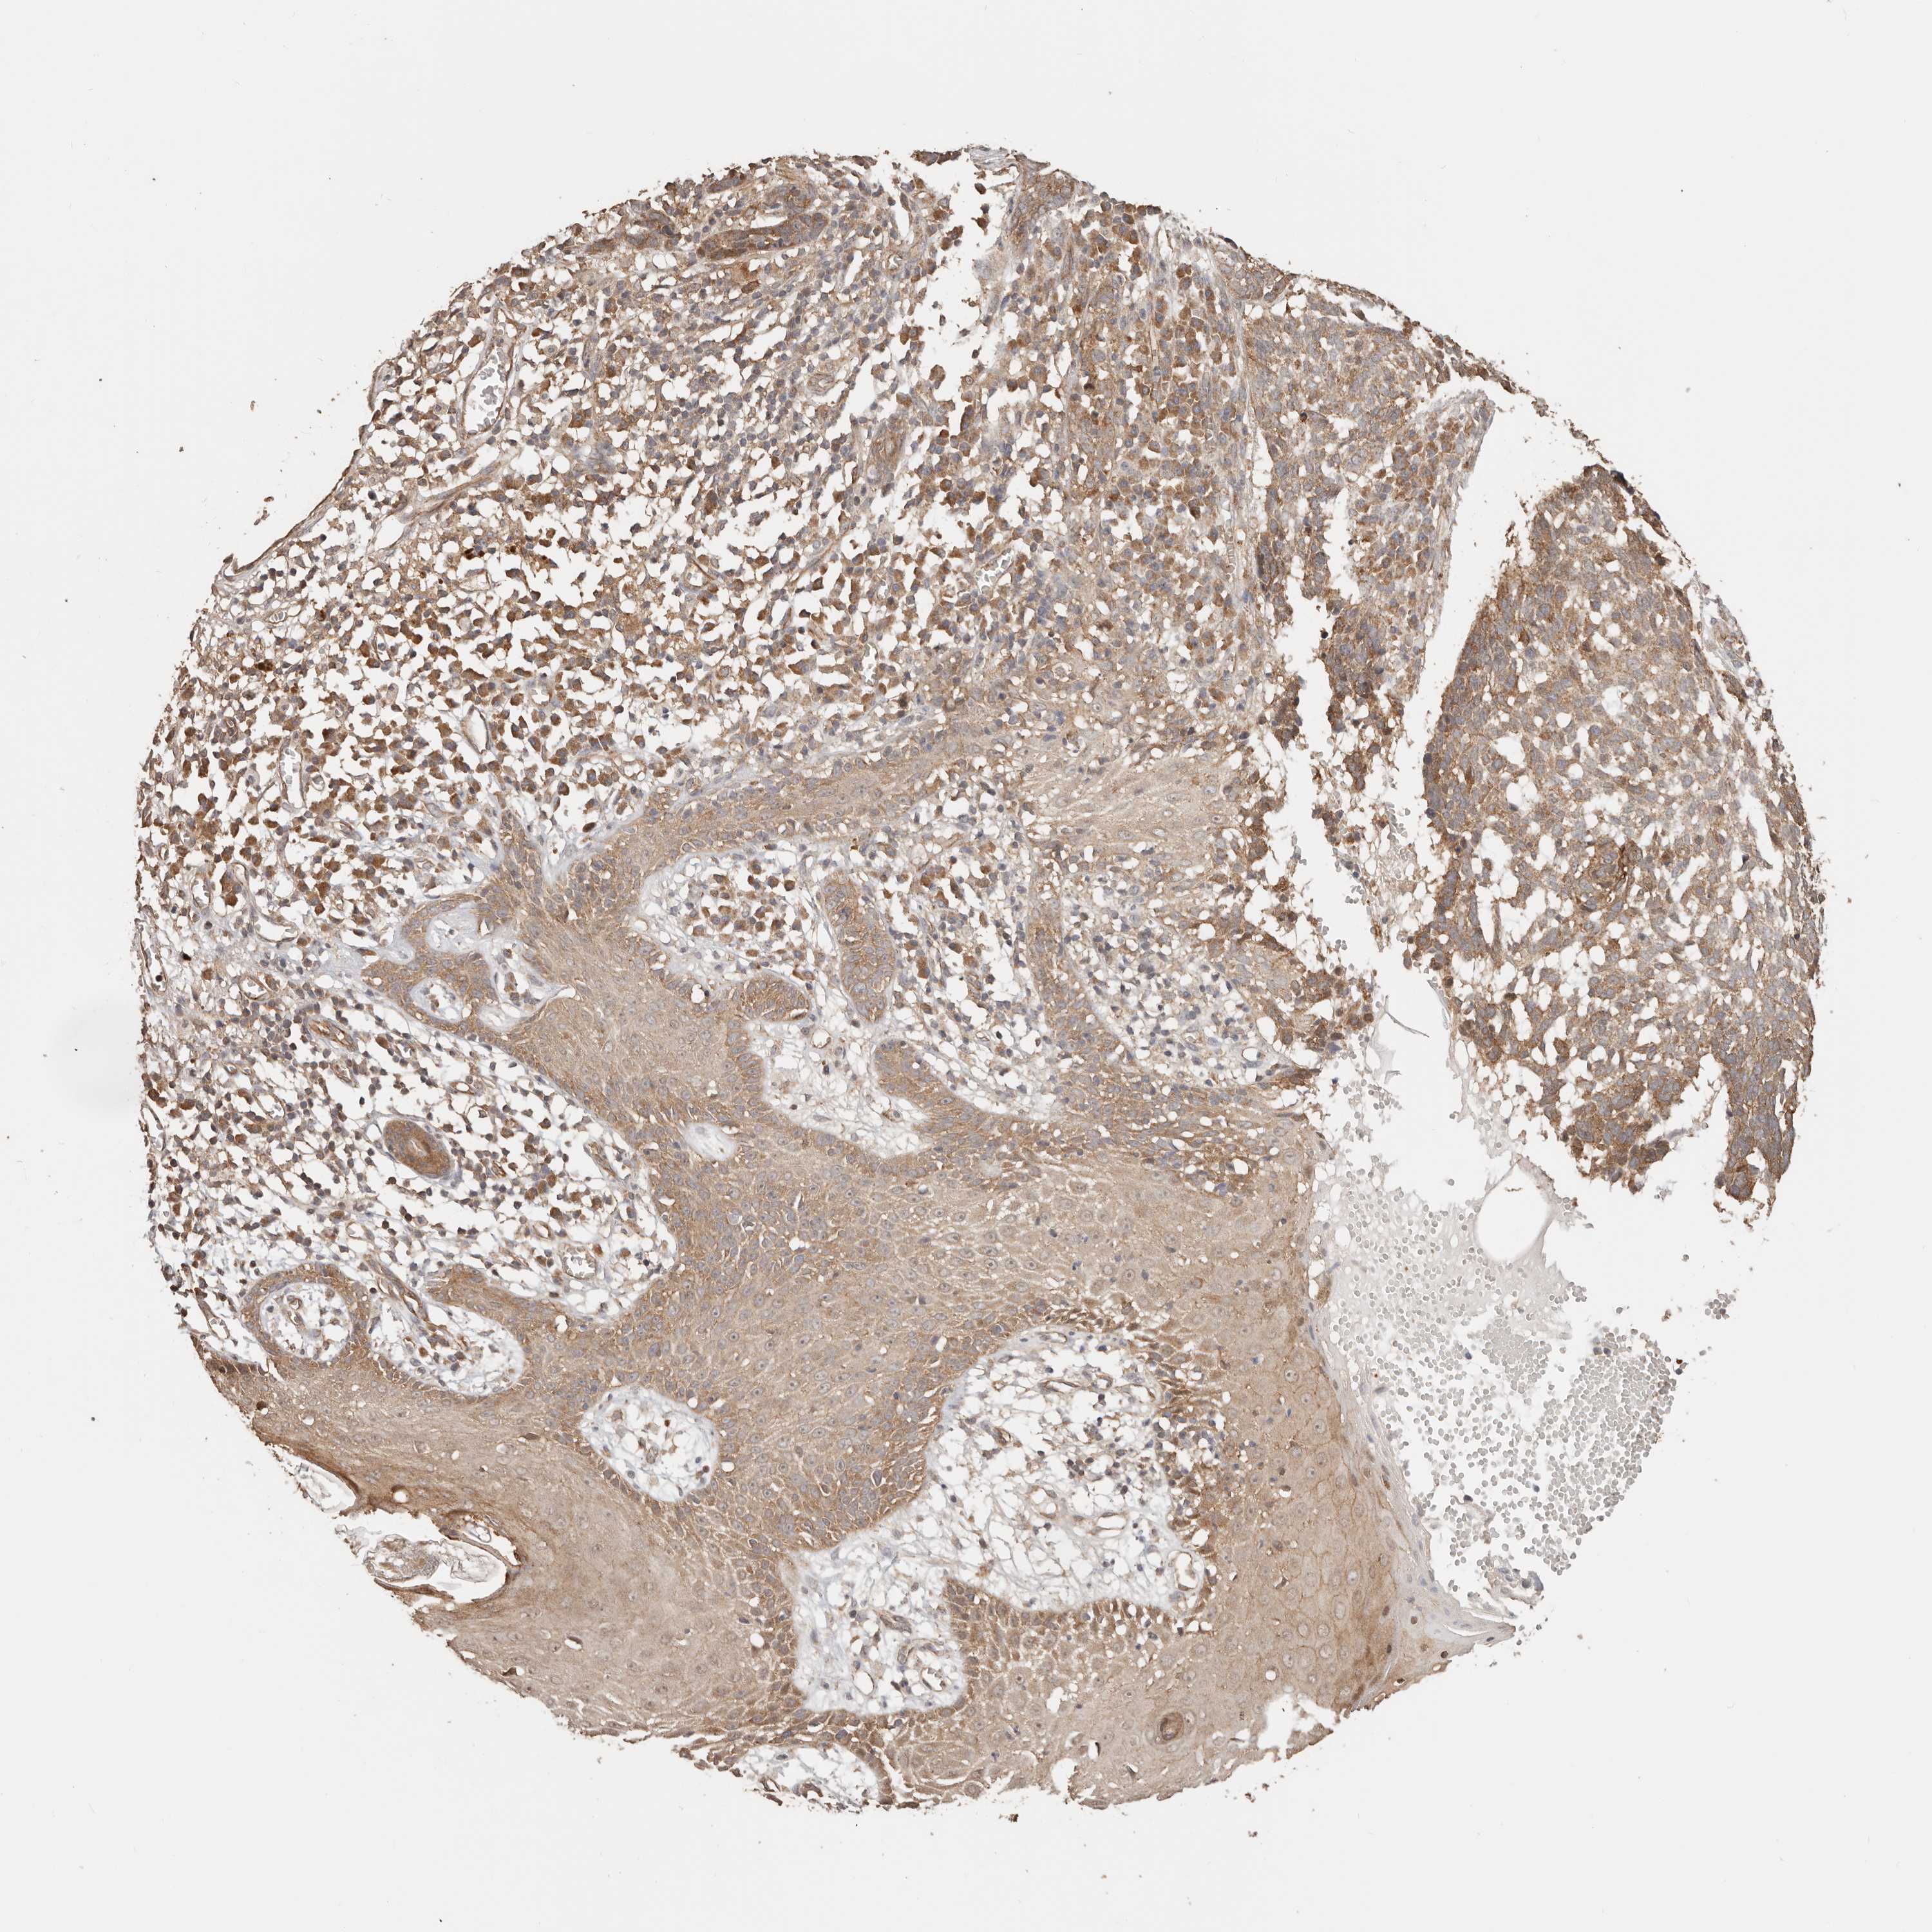

SKIN CANCER - Protein expressioni

A mouse-over function shows sample information and annotation data. Click on an image to view it in a full screen mode. Samples can be filtered based on level of antibody staining by selecting one or several of the following categories: high, medium, low and not detected. The assay and annotation is described here.

Antibody staining in the annotated cell types in the current human tissue is reported as not detected, low, medium, or high, based on conventional immunohistochemistry profiling in selected tissues. This score is based on the combination of the staining intensity and fraction of stained cells.

Each image is clickable and will lead to virtual microscopy that enables deeper exploration of all samples and also displays staining intensity scores, fraction scores and subcellular localization as well as patient and tissue information for each sample.

Basal cell carcinoma

Squamous cell carcinoma, NOS

Squamous cell carcinoma, metastatic, NOS

Adnexal tumor, benign